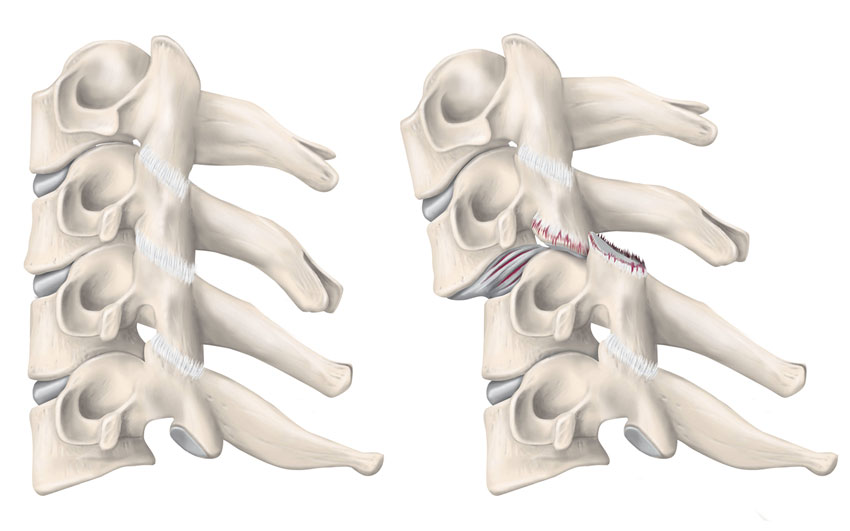

Luxationer/frakturer av fasettlederna

Vid luxationer av fasettlederna rör sig den inferiora fasetten tillhörande den kraniala kotan över den superiora fasetten tillhörande den kaudala kotan på grund av hyperflexion med distraktion. Den anterolistes som skapas kan orsaka kompression av ryggmärg/nervrötter och neurologisk påverkan. Luxationen kan vara uni- eller bilateral och med eller utan fasettledsfraktur. Bilaterala skador är allvarliga och orsakar ofta kompression av ryggmärgen medan en unilateral luxation företrädesvis påverkar den utpasserande nerv­roten. Fasettledsluxation med ryggmärgspåverkan kräver akut reponering med avlastande skallsträck. Bilaterala luxationer är höggradigt instabila även efter reponering. Unilaterala luxationer är, förutsatt att den kontralaterala fasettleden är oskadad, mer stabila [17]. Fasettledsluxationer är tillsammans med C1–C2-frakturer samt frakturer genom foramen transversum en av de skador som förknippas med skada på arteria vertebralis. Vilka patienter som ska screenas för artärskador vid frakturer i halsryggen är omdebatterat [18].

»Hangman’s fracture« med fraktur av bakre kotbågarna. »Potentiellt instabil.

»Burst«-fraktur där fragment dislokerat in mot spinalkanalen. Kan vara instabil.

»Teardrop«-fraktur av extensionstyp. Skada på ALL med ett avulsionsfragment. Stabil.

»Teardrop«-fraktur av flexionstyp. Fraktur som sträcker sig igenom kotan, genom disken och de bakre ligamenten. Instabil.

Fasettledsluxation. Instabil.